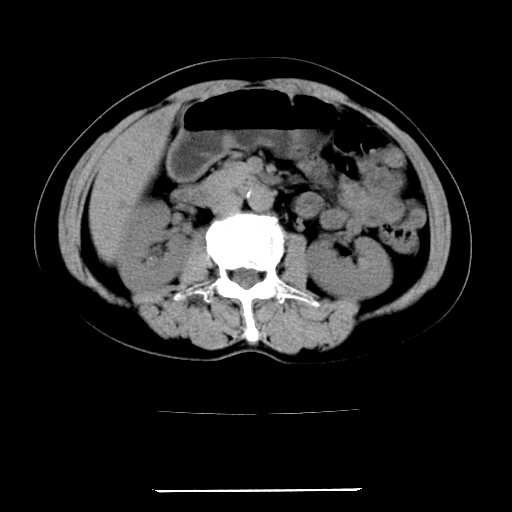

标题: CT22301:女,67岁,上腹部疼痛一周伴皮肤黄染,无发热。 [打印本页]

女,67岁,上腹部疼痛一周伴皮肤黄染,无发热。

1、肝门高密度影下层面和胰头层面可见轻度胆管扩张,而静脉和延迟期均未见扫描完胰头,不能完全排除胰头占位。2、肝门部高密度影,考虑钙化或结石。